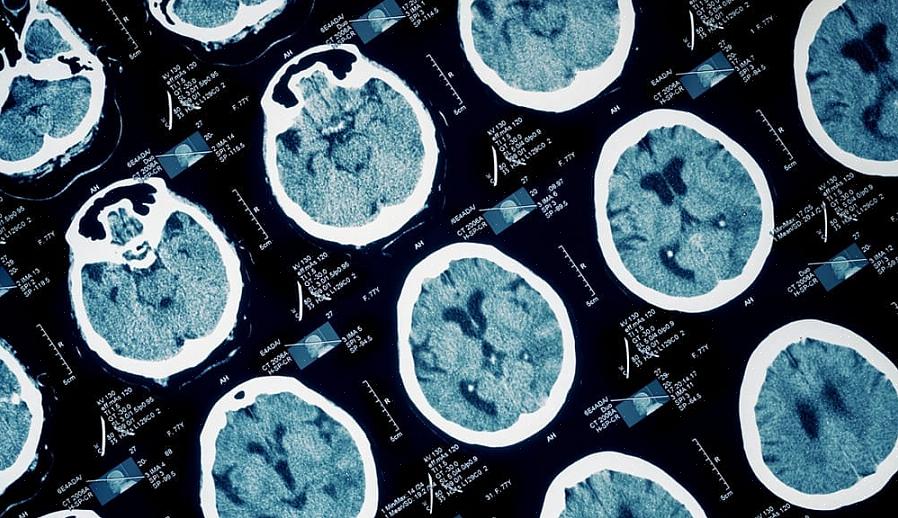

עובדה מעניינת אחת היא שכמעט 8% מהמוח שלנו מורכב מחומצה דוקוסהקסאנואית זו (DHA). חומר זה מבצע פונקציות חיוניות במבנים הנוירונים שלנו. בנוסף, מחקרים מראים כי אומגה 3 חיונית להתפתחות אופטימלית של העובר. אכילת תזונה עשירה בתרכובת זו במהלך ההריון קשורה לאינטליגנציה וביצועים קוגניטיביים גבוהים.

מחקרים על ההשפעה של אומגה 3 על המוח שלנו לא יכלו להיות חיוביים יותר. בבדיקות מעבדה, מדענים גילו שעכברים שקיבלו תוספי אומגה 3 מראים פלסטיות מוחית טובה יותר. הם גם מראים רמה גבוהה יותר של סינפסות בין תאי עצב, כמו גם קישוריות טובה יותר.